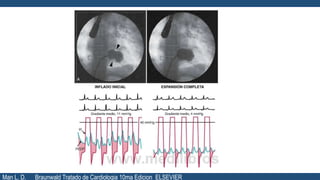

Tratamiento

• EL TRATAMIENTO DEBE DECIDIRSE

BASANDO EN

• Características clínicas

• Anatomía de la válvula

La indicación de intervención se debe limitar

a los pacientes con estenosis clínicamente

significativa.

COMISUROTOMIA

MITRAL PERCUTÁNEA

(CMP)

CIRUGI

A

REPARACIÓN O

SUSTITUCIÓN